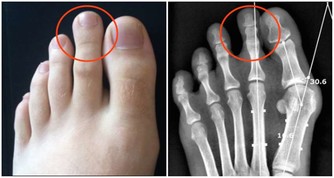

3、牙齒頸部的楔狀缺損想像一下如果總以錯誤的方式刷牙,那麼牙齒頸部的缺損就會愈來愈大,

即導致牙齒的「楔狀缺損」。

平時常常牙痛,冷水刷牙或遇冷時,牙齒敏感,就有可能是因為牙齒頸部的「楔狀缺損」引起的,

它是牙齒唇頰側頸部硬組織發生緩慢消耗所致的缺損,由於這種缺損常呈「楔形」因而得名。

長期橫著刷牙,大力刷牙或者牙刷過硬,都可能造成牙齒頸部的磨損,形成「楔狀缺損」。

一般在楔狀缺損症狀較輕時,不會有明顯痠痛感,這時不需要進行處理。

只要注意不要橫著刷牙,選擇小頭較軟的牙刷,小心保護即可。